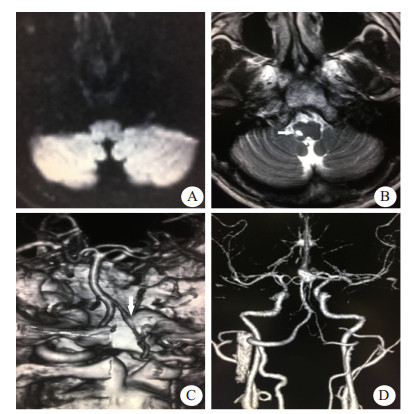

| A:首次磁共振检查DWI阴性;B:半年后复诊T2WI可见右侧延髓软化灶;C:首次头颅CTA可见左侧椎动脉线珠样改变(箭头示);D:半年后复查CTA椎动脉夹层愈合 图 1 例1患者影像学检查结果 |

1 资料与方法患者1,男性,29岁,因“后颈部疼痛3 d,眩晕、吞咽困难2 h”就诊急诊。患者3 d前无明显诱因下出现后颈部胀痛,疼痛持续性,2 h前出现眩晕,吞咽困难,流涎,持续无好转,无复视,无耳鸣及听力减退,无肢体瘫痪,无大小便障碍。既往体健,否认遗传病及传染病史,否认外伤及药物滥用。查体:意识清楚,口齿不清,两侧瞳孔等大,对光反射存在,眼球活动自如,自发眼震,鼻唇沟对称,伸舌居中,口腔分泌物多,左侧咽反射迟钝,颈软,心律齐,四肢肌张力正常,四肢肌力Ⅴ级,左侧指鼻试验、跟膝胫试验不稳,交叉性感觉障碍,两侧病理征阴性。患者疑似急性脑血管病,不能确诊,故仍启动溶栓绿色通道,立即完善血常规、超敏C反应蛋白(CRP)、肝肾功能、血糖、凝血酶原时间(PT)、国际标准化比值(INR)、肌酶均提示正常范围。头颅CT平扫未见明显异常。头颅DWI未见明显异常。头颅CT血管造影(CTA)可见左侧椎动脉局部线珠样改变,考虑VAD。最后诊断Wallenberg综合征、VAD。当时患者仍为溶栓治疗时间窗内,将静脉溶栓事项充分告知,患者及家属未选择溶栓治疗,遂予以阿司匹林、阿托伐他汀、异丙嗪、奥美拉唑治疗,次日眩晕减轻,仍有吞咽困难,患者家属要求转入某大学附属医院,之后继续采用阿司匹林、阿托伐他汀等药物治疗,辅以康复锻炼。半年后来我院复诊,患者吞咽功能恢复,遗留肢体感觉障碍,头颅MRI可见延髓软化灶,颈部血管CTA提示夹层愈合。本病例资料的报道已获得患者知情同意。

例1患者急性起病,表现为眩晕,吞咽障碍,查体有自发性眼震、交叉性感觉异常、共济运动不稳,提示急性延髓病变,病变性质不明确。患者青年男性,且无明显脑血管病危险因素,发病前有颈部疼痛,为防止误诊、漏诊,立即完善头颅DWI和CTA检查。其中头颅CTA检查发现左侧VAD,为病灶责任血管,虽然DWI为阴性,仍然诊断急性延髓梗死。目前缺乏颈部动脉夹层所致缺血性脑卒中患者进行静脉溶栓的有效性和安全性方面的研究,部分研究提示发病4.5 h内运用rtPA静脉溶栓可能是安全的[8-9]。本例患者及家属均未选择溶栓治疗方案,采用阿司匹林、阿托伐他汀治疗,所幸患者病情未进一步进展加重。